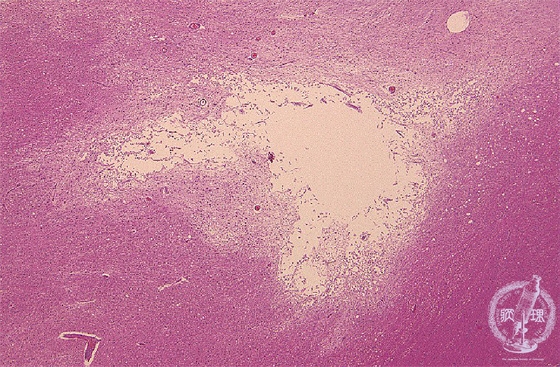

Microscopic findings (H.E. low magnification): Old infarction demonstrated destruction of the brain parenchyma with cavitation and accumulation of many macrophages as a result of liquefactive necrosis.